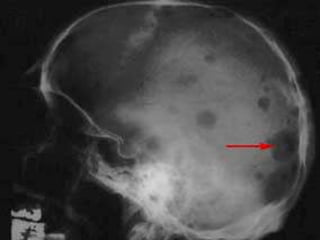

Comprometimento Ósseo

EXAMES COMPLEMENTARES Rx de esqueleto Em casos selecionados: TAC, RNM NCCN Practice guidelines in Oncology – v 2.2009